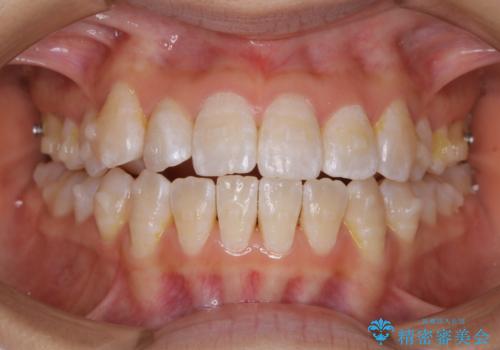

前歯のがたつきとオープンバイト:インビザラインでまとめて治す

- 噛み合わせと、前歯のがたつきが気になるとご相談にいらした方です。インビザラインFULLで綺麗な歯並びと噛み合わせを作ることが出来ました。

オープンバイトの方への治療は、通常抜歯を行いワイヤーによる矯正治療を行うことが多いですが、今回はインビザラインの特性を生かし、非抜歯にて綺麗な歯並びを作ることが出来ました。